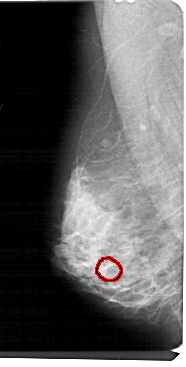

FILE: A_1449_1.LEFT_MLO.OVERLAY

TOTAL_ABNORMALITIES 1

ABNORMALITY 1

LESION_TYPE CALCIFICATION TYPE AMORPHOUS DISTRIBUTION CLUSTERED

ASSESSMENT 4

SUBTLETY 2

PATHOLOGY BENIGN

TOTAL_OUTLINES 1

BOUNDARY